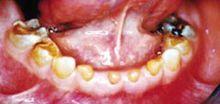

科學家成功克隆乳光牙基因遺傳性乳光牙本質又稱遺傳性牙本質發育不全,俗稱大黃牙,是一種常見的口腔疾病,兒童發病率約為1/7000。其主要表現為牙本質的鈣化異常和缺陷,牙釉質發育正常,但易從牙本質表面分離脫落,使牙本質外露而致牙冠磨損。患者牙齒萌出時,其形態大小可正常,但牙冠呈微黃色半透明,並逐漸變成乳光色或淺黃色外觀。

牙冠呈半透明乳光色可為淺黃色也可為棕黃色釉質很易折失特別是切牙切緣和磨牙的合面極易發生釉質折失牙本質暴露牙本質暴露後極易被磨損表現為重度磨耗後的牙本質平面的出現。